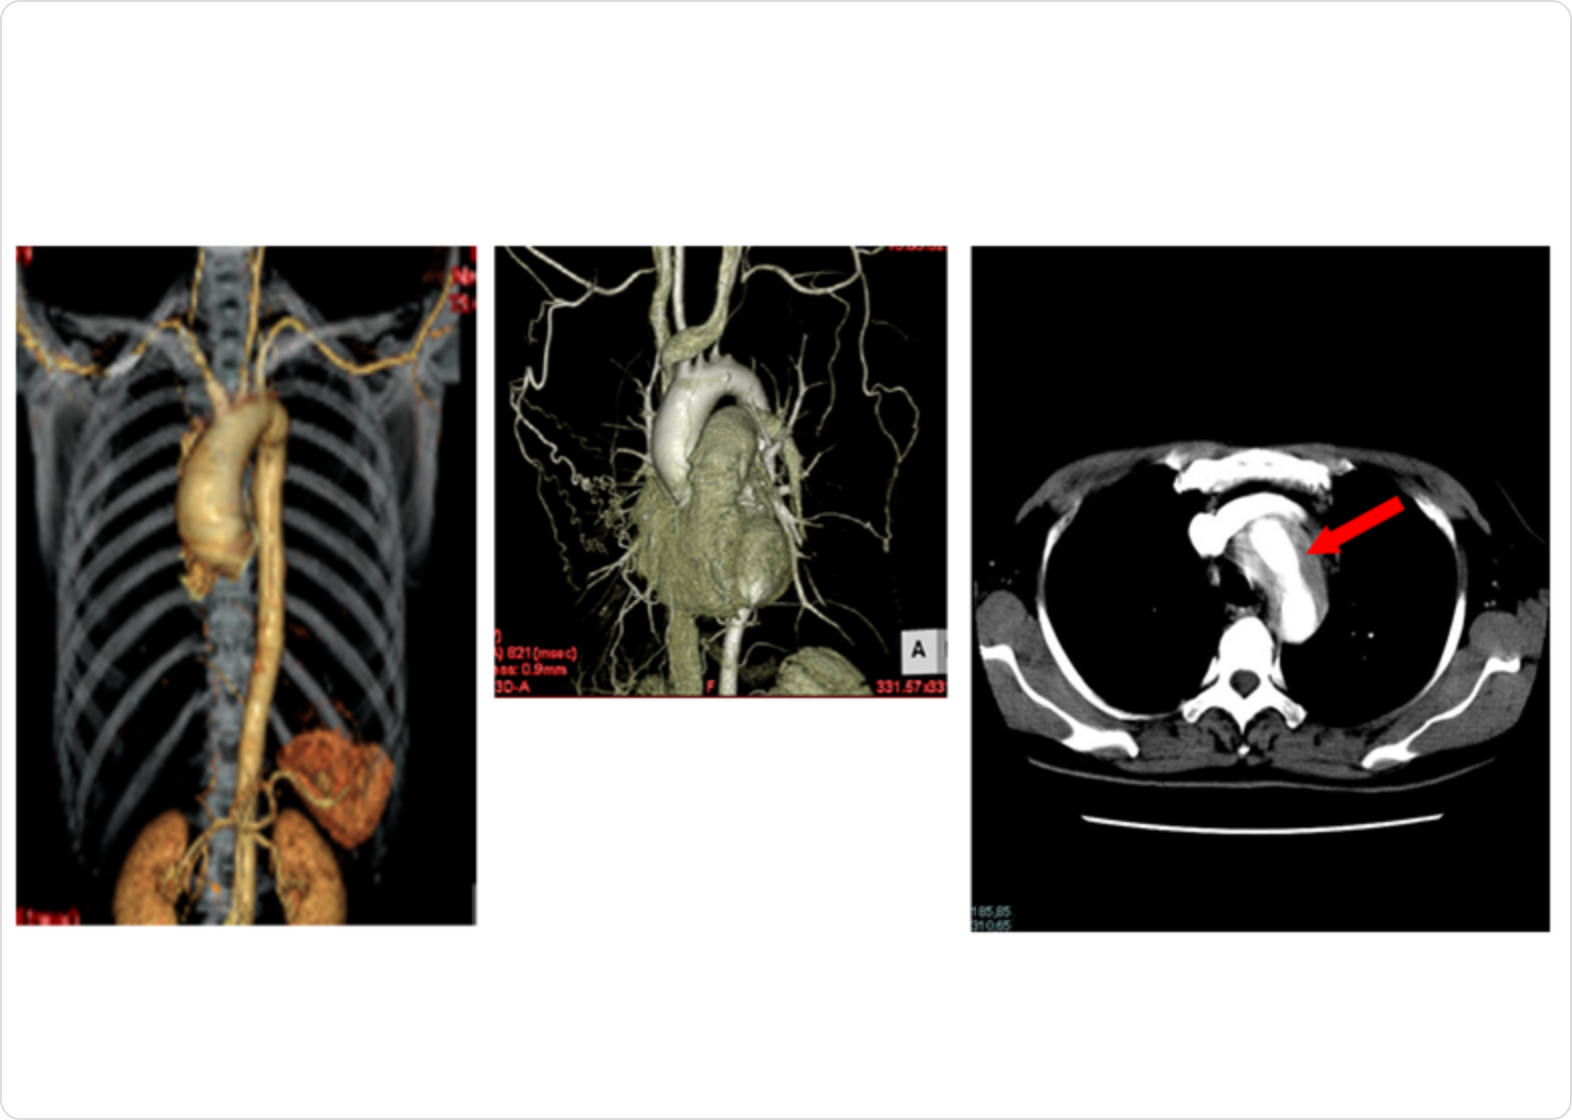

CT

CTの画像をコンピュータを使って3次元的に再構成すると、血管の様子がよくわかります。安全性の高い検査ですが、まれに造影剤にアレルギー反応を起こす方がいます。左側の画像では上行大動脈の拡張、中央では左鎖骨下動脈の閉塞、右側は断層写真で大動脈の壁が厚くなっていることが分かります。